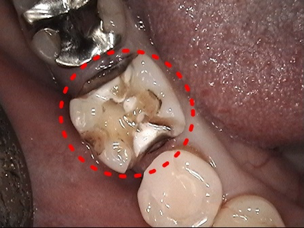

1. 患歯の切削

治療箇所を削ります。金属が入っていた部分をやり替える場合は外して形を整えます。

3. 設計

コンピューターの3D画面上で修復物を設計します。

モニター上で歯の形態や噛み合わせの調整を、あらゆる角度から行い、

理想的な形にしていきます。

設計後は様々な色のセラミックブロックから最適な色のものを選定します。